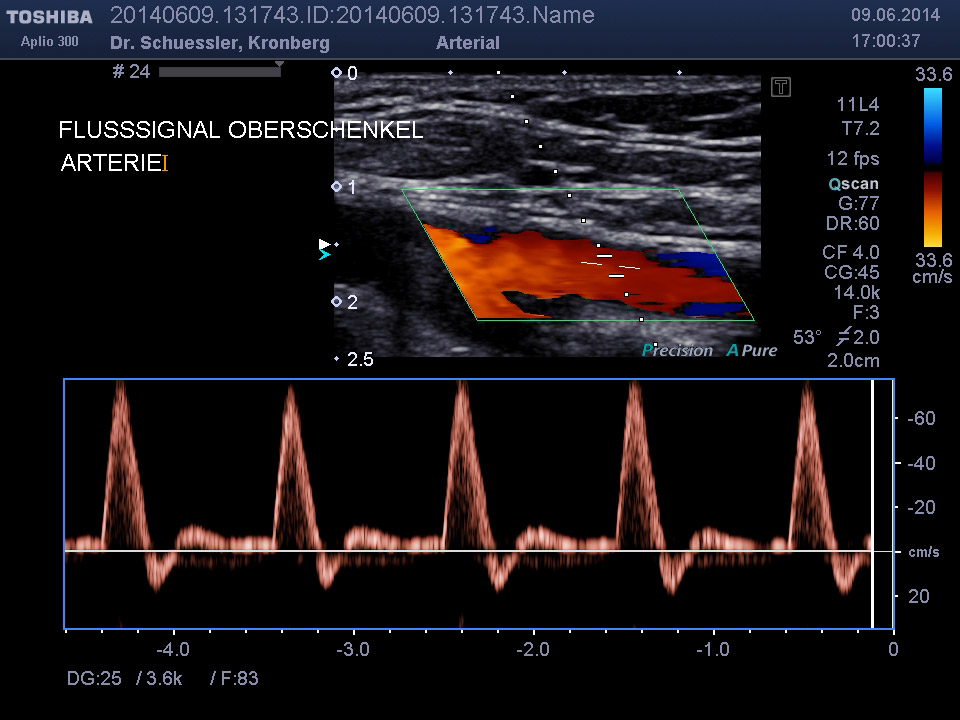

Die farbkodierte Duplexuntersuchung der Gefäße ist ein Ultraschallverfahren und gibt u.a. Auskunft über Verkalkungen, Einengungen, Verschlüsse oder Thrombosen im Bereich der Arterien und Venen.

Die Untersuchung wird angewandt zur Diagnostik von Verengungen in den hirnversorgenden Arterien, Erweiterungen (Aneurysmen) oder Verengungen der Bauchschlagader, Verengungen der Nierenarterien bei Bluthochdruck,  Venenthrombosen und zur Bestimmung des Gefäßrisikoprofils.